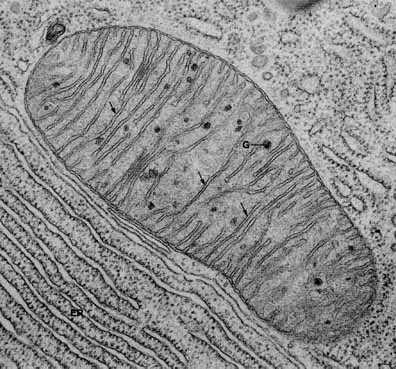

Дефекты окисления жирных кислот – болезнь, от которой страдает один новорожденный ребенок из трех тысяч. Подобные расстройства могут привести к повреждению мышечных тканей, в том числе, сердечной, если больной не соблюдает строжайшую диету в течение всей жизни. Как другие тяжелые нарушения обмена веществ – диабет второго типа и ожирение, - дефекты окисления жирных кислот связаны с дисфункцией митохондрий в клетках. Напомним, именно в митохондриях молекулы, полученные организмом с пищей, превращаются в энергию, используемую клеткой для жизнедеятельности.

Однако один из главных потребителей этой молекулы – фермент PARP1. Исследования показали, что, сокращая количество последнего, например, с помощью медикаментов Paribs, можно добиться увеличения количества свободных молекул NAD+, и, соответственно, – белка SIRT1. Действительно, у крыс с недостатком фермента PARP1 наблюдается активация белка SIRT1: митохондрии функционирует гораздо лучше, сжигают жирные кислоты, не прибегая к использованию глюкозы. Результат: защита от нарушений обмена веществ у этих животных гораздо более эффективна.